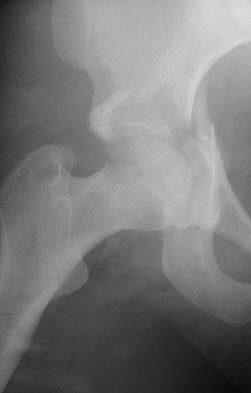

Describe this fracture?

DUVERNEY - isolated iliac wing fracture - direct trauma to iliac crest - usually lateral compression * Consult Ortho in ED - can extend into acetabulum, and may require ORIF - can be associated with major -non-pelvic injuries